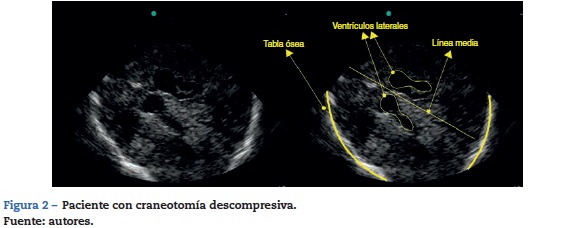

En pacientes con craneotomía descompresiva (fig. 2) se facilita la valoración de parénquima cerebral, puesto que los artefactos y la sombra acústica ósea no se presentan. En estos pacientes el transductor se posiciona en los sitios donde no hay presente tejido óseo y no requiere una referencia anatómica específica. En este grupo de pacientes se ha reportado seguimiento de tamaño de hematomas intracerebrales, posición de catéteres de derivación17 y monitoreo o seguimiento de la desviación de línea media con el tratamiento instaurado18.